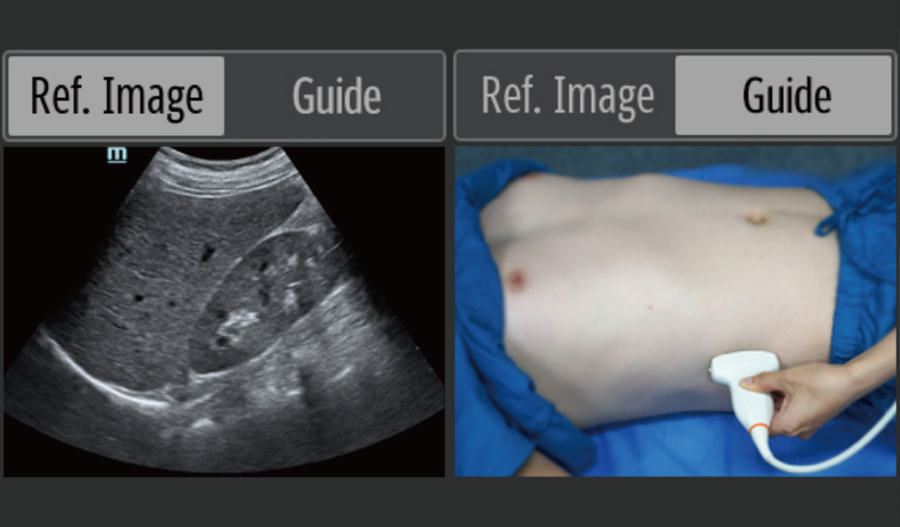

EcografÃa en el punto de atenciÃģn (POCUS)

Las funciones integradas de ecografÃa fundamentan el diagnÃģstico in situ, con una guÃa de operaciÃģn inteligente para facilitarlo.

- ImÃĄgenes de referencia y guÃas de operaciÃģn

- Sonda de matriz en fase: alta resoluciÃģn, ampliamente utilizada